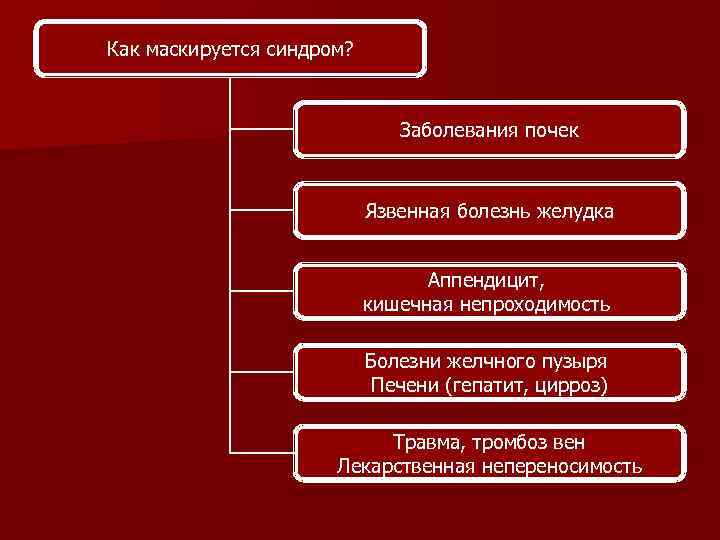

Как маскируется синдром? Заболевания почек Язвенная болезнь желудка Аппендицит, кишечная непроходимость Болезни желчного пузыря Печени (гепатит, цирроз) Травма, тромбоз вен Лекарственная непереносимость

Как маскируется синдром? Заболевания почек Язвенная болезнь желудка Аппендицит, кишечная непроходимость Болезни желчного пузыря Печени (гепатит, цирроз) Травма, тромбоз вен Лекарственная непереносимость